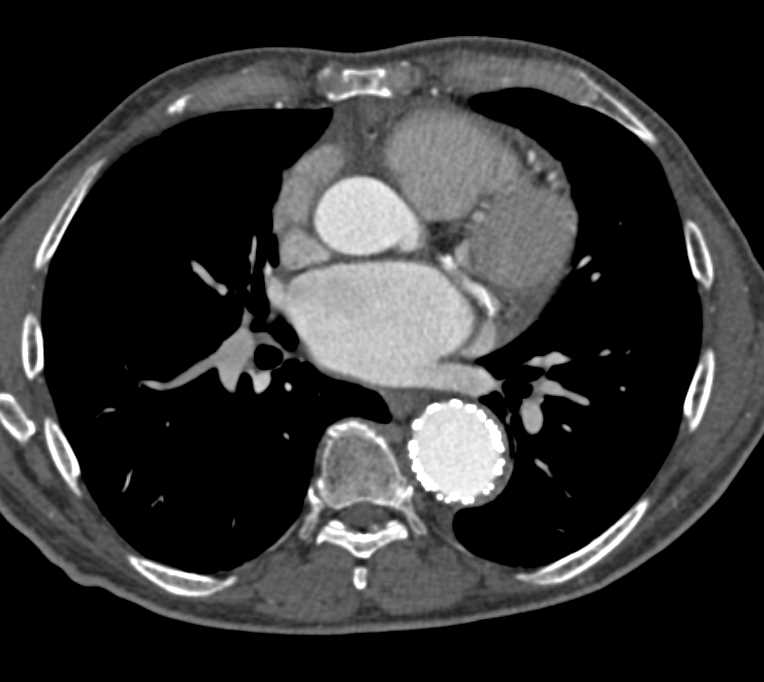

Occluded Right Common Iliac Artery and Peripheral Vascular Disease (PVD)